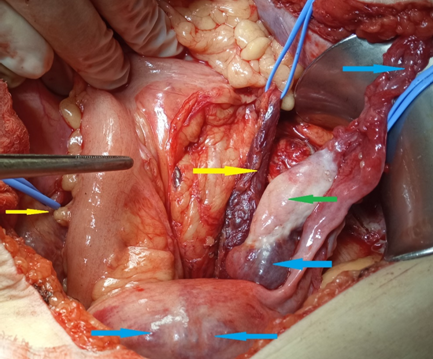

Κίτρινα βέλη — Φλεγμαίνουσες εκκολπώσεις στο εξω-κοιλιακό εντερικό τμήμα. Πράσινο βέλος — Υγρή συλλογή (Ευγενική παραχώρηση Dr. V. Penopoulos)

Πράσινο βέλος – εστιακή εξέλκωση κολικού βλεννογόνου. Κίτρινο βέλος – οίδημα και λεμφοκυτταρική διήθηση υποβλεννογόνιου χιτώνα (Ευγενική παραχώρηση Dr. V. Penopoulos)

Πράσινο βέλος – περιφλεβιδική λεμφοκυτταρική διήθηση σε υποβλεννογόνια θέση (Ευγενική παραχώρηση Dr. V. Penopoulos)